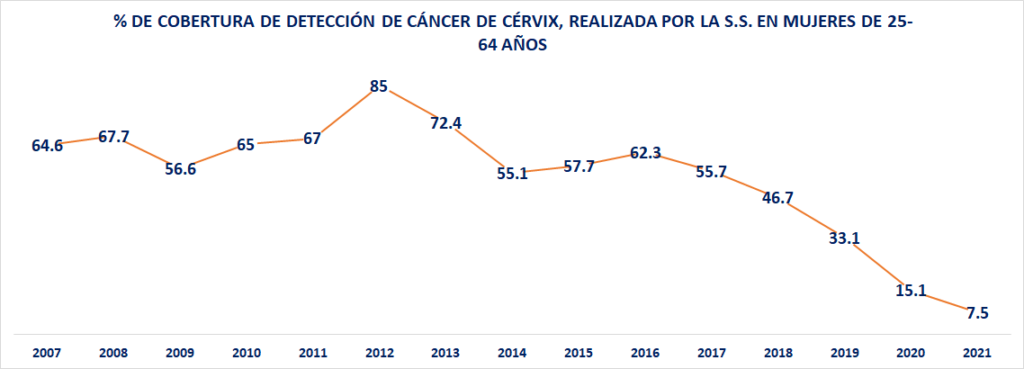

El otro indicador preocupante es la drástica caída en el porcentaje de cobertura de detección realizada por la Secretaría de Salud, en mujeres de 25 a 64 años de edad. En este caso, el indicador de 2007 fue de 64.6%; en el 2012 se llegó al máximo histórico con 85%; sin embargo, para el año 2018, el último del gobierno de Enrique Peña Nieto, ya se había desplomado a únicamente 46.7%

La caída se ha mantenido: 33.1% de detección oportuna en el 2019; 15.1% en el año 2020; y un indicador proyectado para el 2021 de únicamente 7.5%.